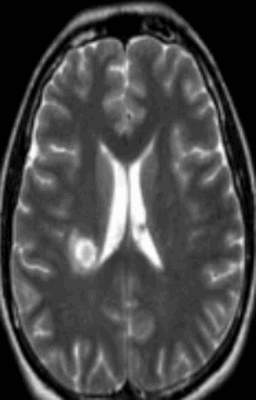

Признаками рассеянного склероза головного и спинного мозга на МРТ изображениях будут:

- слабовыраженные очаговые изменения, повышение сигнала Т2;

- типичное вовлечение спинного мозга;

- распространенность не более двух сегментов;

- поражения латеральных или задних столбов белого вещества с возможным вовлечением центральных отделов;

- в острой фазе утолщение спинного мозга;

- в хронической фазе слияний очагов;

- атрофические изменения в мозге - заместительная гидроцефалия.